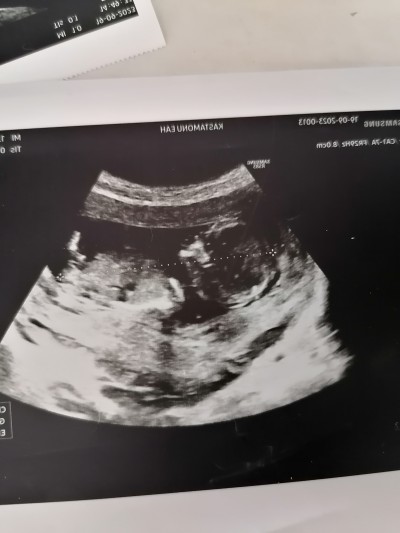

13 haftalık 3 gunluk doktora cinsiyet hakkında hiçbirsey söylemedi merak ediyorum nub teorisi dogruluk payı cok oldugunu duydum sizce ne olabilir cinsiyeti